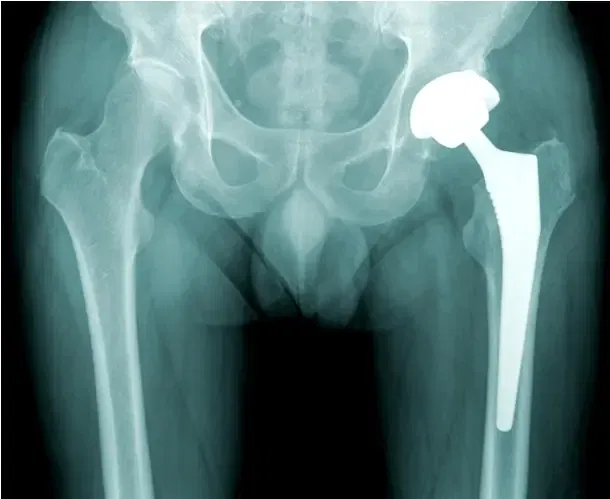

Según un estudio de 2014 de la Academia Americana de Cirujanos Ortopédicos, más de 2,5 millones de estadounidenses viven con una cadera artificial.

No sería de extrañar que esa cifra haya aumentado significativamente desde entonces, ya que la tasa de incidencia de las operaciones de revisión de cadera sigue creciendo. Al fin y al cabo, son muy eficaces para recuperar la movilidad, eliminar el dolor y mejorar la calidad de vida de los pacientes.

Es una operación que se realiza para reparar una articulación protésica que se ha dañado con el tiempo. Puede deberse al desgaste normal, al aflojamiento, a una fractura, a una luxación o a una infección.

Los implantes, ya sean cerámicos, metálicos o de otro material, no son permanentes, aunque suelen durar entre 20 y 25 años. En cualquier caso, tarde o temprano será necesaria una revisión.